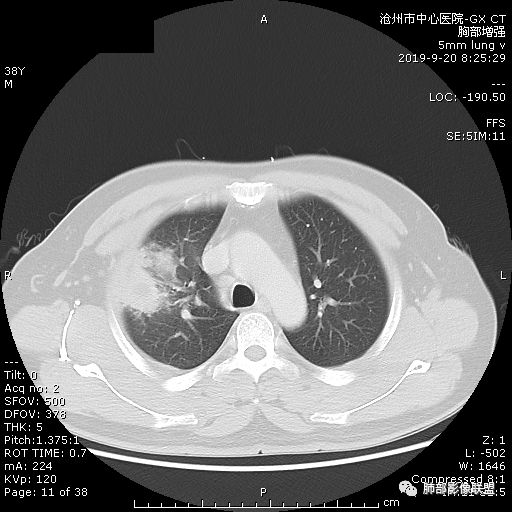

青年男性,肿瘤指标无异,右上中肺团片影,形态不规,跨叶生长,

年轻男性,咳嗽2月,痰中带血,胸痛,炎症指标稍高,肿标正常。影像,右肺上叶不规则团块影,浅分叶,伴边界不清磨玻璃影,从外周向内分布,局部胸膜增厚,病灶中央坏死,坏死边界尚清,空洞形成,空洞内壁光滑;考虑炎性肉芽肿性病变,结核可能,鉴别恶性肿瘤及真菌感染。病灶分布特点不考虑隐球。

右肺上叶不规则病灶,密度不均,有分叶,边缘不清,中央有坏死,坏死壁尚光滑,增强壁有强化,病灶有外朝内,整体收缩为主,慢性病程,考虑炎性病变,肺脓肿或者结核,淋巴结肿大,支气管截断,胸膜脂肪间隙变窄,加个鉴别恶性肿瘤。

右肺上叶不规则团块影,边缘欠清晰,增强扫描坏死区边界清晰,水平裂牵拉上移,考虑机化性肺炎并脓肿,鉴别:结核、肺癌。

38岁,男性,慢性咳嗽2月,右胸痛8天,无发热。白细胞高,肿瘤标志物不高。右上肺不规则块状影,周围有磨玻璃影,边界模糊,整体有膨胀感,分叶,与胸膜糊墙,可疑栽赃,增强肿块中央坏死,边界清,周边强化明显,强化区有低密度影,壁不规则,跨叶生长,支气管截断,伴支气管扩张,综合考虑腺癌

晨读:右肺上叶不规则团块,深分叶,膨胀为主,有部分收缩,叶间裂牵拉上移,内多液化坏死,有支气管扩张,右肺上叶大支气管近端通畅,远端堵塞,说明肿块来源于外周,纵隔及右肺门淋巴结肿大,胸膜糊墙为主,年轻人,肿标不高,炎性指标高,综合考虑炎性肉芽肿放前面脓肿,结核,肿瘤放后面。

首先病灶示:跨尖、后、前三段,局部突入中叶;大家理解一下:是不是光滑的地方有叶裂,毛糙的地方没叶裂。

第二种是局部叶裂畸形或发育不全、有缺陷,病灶经缺陷处侵犯蔓延,事实上叶裂缺并非少见,影像观察应当结合冠矢状位。

假如一个病灶直接跨越胸膜侵犯过来,应该边缘都很毛糙,不应该是最突出的地方毛糙,应该是逐步毛糙过去的,充其量越到外面毛糙越少;但事实上今天这个病变是一个很突兀的毛糙,突然间嘎然而止的毛糙;所以这个提示应该是从缺陷处跨过来的;还有今天的这个病例,病灶跨叶的部分对附近的胸膜是推移的,附近的胸膜还是很光滑,但是跨叶的病灶区很毛糙,提示跨叶部分存在胸膜缺陷可能;一般来说恶性肿瘤直接侵犯到对侧还是少的,如果这个地方你怀疑有缺陷,跨胸膜在诊断良恶性价值就不大了。